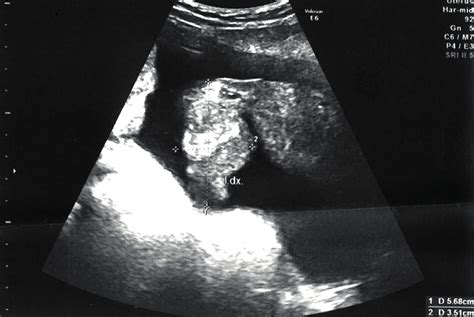

Ultrazvukové měření a jeho interpretace

Ultrazvukové měření biometrických parametrů u plodu je metoda, která je ovlivněna několika faktory. Mezi ně patří spolupráce miminka, jeho poloha, pohybová aktivita a přístupnost k ultrazvukovému zobrazení. Stejně tak je metoda ovlivněna subjektivním měřením každého konkrétního lékaře. Není neobvyklé, že každý lékař může v danou chvíli naměřit lehce odlišné hodnoty téhož parametru, aniž by se jednalo o chybu.

Ultrazvukové měření hmotnostního odhadu má obecně chybovost 15-20 %. Hodnoty, které jsou uváděny, jsou obvykle v mezích normy.

Ultrazvukový screening ve druhém trimestru, prováděný mezi 18. a 22. týdnem těhotenství, je jedním z nejdůležitějších vyšetření prenatálního vývoje. Dokáže odhalit až 90 % strukturálních vývojových vad.

Během tohoto ultrazvuku lékař kontroluje správný vývoj miminka, anatomickou stavbu orgánů, délku děložního hrdla, umístění placenty, průtok krve pupečníkem, množství plodové vody, činnost srdce, vývoj mozku, páteř, držení končetin a prstů a velikost hlavy.